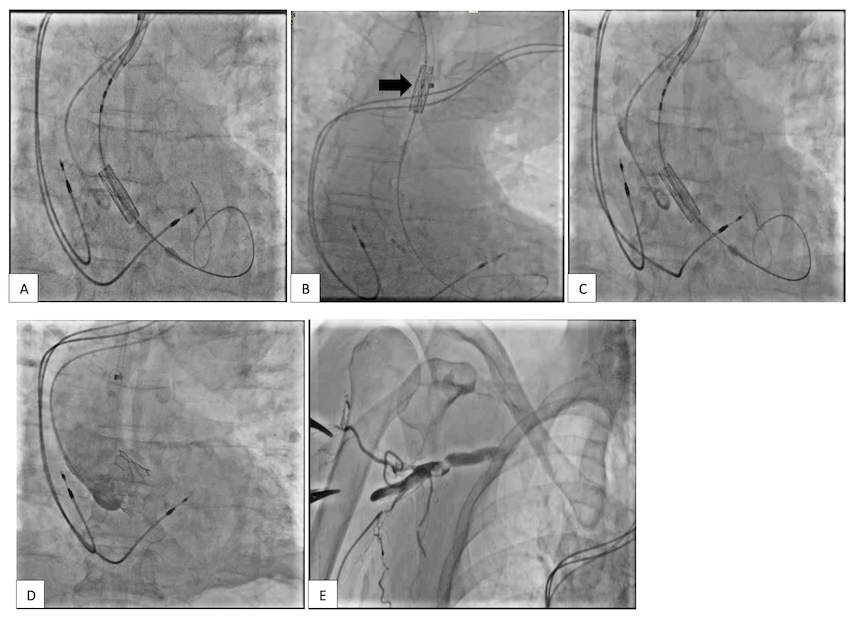

Under anesthetic sedation, a right radial arterial line and left radial pigtail access was established, followed by ultrasound-guided access to the right axillary artery. A single ProGlide pre-closure suture was deployed. The aortic valve was crossed, and a small Safari wire placed in the LV. A 14-Fr eSheath was inserted (Figure 2A). A 26-mm S3 Ultra valve was taken and loaded with the sheath partially withdrawn. Using angulation of the Edwards Commander system pusher catheter along with rotation of the whole apparatus, a good position on the outer curve of the aorta was established allowing co-axial positioning of the Edwards valve (Figure 2B). This was then implanted under rapid pacing through the LV wire, and as is typical for the transaxillary approach, did not rise more than a millimeter. The final results were very good (Figure 2C), with resolution of her aortic stenosis and no aortic regurgitation. The sheath was removed and the access site closed with the ProGlide and an 8-Fr Angioseal vascular closure device, with a very good result. There were no procedural complications, and the patient went home the following day.

A second attempt at TAVI was made under anesthetic sedation. A Vygon arterial line was placed in the right radial artery. Left radial access was used for secondary access. Both required ultrasound guidance in view of his calcific peripheral vascular disease. Right axillary artery access was gained under ultrasound guidance. Initially, a 6-Fr sheath was inserted into the right axillary artery. Two ProGlide sutures were deployed for pre-closure. A 26 S3 Ultra valve was advanced into position across the annulus. Using the retroflex of the ES commander system, the S3 valve was position to allow co-axial alignment (Figure 4A). Under rapid pacing and balloon expansion, the balloon failed to inflate, suggesting separation of the balloon from the end of the catheter.20 Blood came back into the indeflator. We were able to recapture the valve into the end of the eSheath successfully (Figure 4B) using techniques previously described.20 We then put in a second introducer, and a second 26 mm S3 Ultra valve was used. Articulation of the Flexwheel was applied and excellent co-axial alignment was achieved with the balloon catheter along the outer curvature of the ascending aorta (Figure 4C). This was put in a good position just below the aortic annulus (Figure 4D). The axillary access was closed with two ProGlide sutures, but at the end of the case there appeared to be a poor arterial trace. Angiography revealed arterial dissection at the closure point (Figure 4E). This was dilated with a 5.0 mm coronary balloon. We elected to implant an 8 mm x 37 mm Bentley uncovered stent at the access site. The final result was good with the pulse wave restored with reasonable blood pressure. He was successfully discharged from the hospital after 3 days.